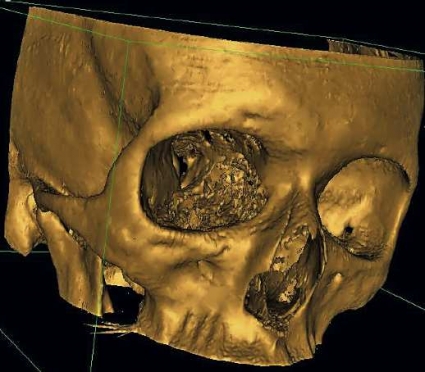

Noggrann klinisk undersökning är av största betydelse i utredningen och en förutsättning för att upptäcka och bedöma de olika komplikationerna, såsom fastklämd extraokulär muskulatur, bulbskada eller synnervsskada. Vid misstanke om fraktur ska ansiktsskelettet undersökas med datortomografi med tunna axiala snitt, och från de axiala snitten görs koronara och sagittala reformaterade serier. Avbildning av ögonhålan i dessa tre plan är nödvändig för diagnostik av orbitaväggsskador och för planering av rekonstruktionen. Tredimensionella bilder ger framför allt en bra visualisering av ansiktsfrakturer utanför orbitan och av implantat vid postoperativa undersökningar.

Dessa undersökningar kan vara av stort värde vid kirurgisk planering, postoperativa kontroller och i undervisning. Emellertid är det med dagens teknik svårt att visualisera de tunna orbitaväggarna på dessa tredimensionella bilder, och orbitaväggsdefekter kan här vara artefakter. För att ägna sig åt rekonstruktiv kirurgi i orbitan krävs vana vid arbete med datortomografiskt bildmaterial. Vidare är ett nära samarbete mellan specialintresserad radiolog och orbitakirurg av stort värde.

En 53-årig kvinna föll ner för en trappa, slog sig i ansiktet och ådrog sig högersidiga orbitafrakturer. Preoperativt fanns inget dubbelseende eller enoftalmus, däremot smärta i ögat vid blickriktning uppåt och lateralt. Preoperativ datortomografi visade en ren blow-out-fraktur av orbitabotten och medialväggen (Figur 2). Defekterna involverade större delen av orbitabotten ända bak till orbitans apex samt den mediala orbitaväggen upp till sutura frontoethmoidalis. Volymbestämning gjordes i mjukvaran Osirix efter att orbitans begränsningar markerats på alla axiala snitt mellan orbitans övre och nedre begränsning (60 snitt). Den skadade sidan uppmättes till 31,3 cm3, att jämföra med den friska sidans 26,0 cm3.